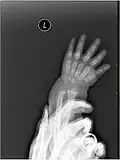

Left hand shown with thumb on left.

The metacarpals form a transverse arch to which the rigid row of distal carpal bones are fixed. The peripheral metacarpals (those of the thumb and little finger) form the sides of the cup of the palmar gutter and as they are brought together they deepen this concavity. The index metacarpal is the most firmly fixed, while the thumb metacarpal articulates with the trapezium and acts independently from the others. The middle metacarpals are tightly united to the carpus by intrinsic interlocking bone elements at their bases. The ring metacarpal is somewhat more mobile while the fifth metacarpal is semi-independent.[1]